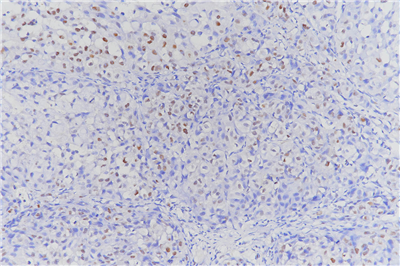

(6)DAB染色3-10min,自来水冲洗,苏木素复染, 1%盐酸酒精分化,显微镜下观察,控制染色程度。

(10)通过显微镜采集分析样本相关部位,计算凋亡率。